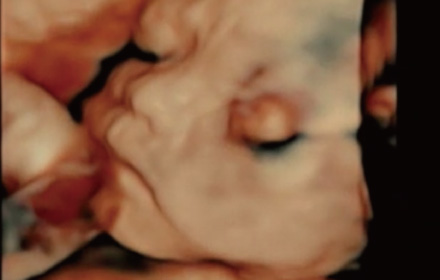

胎児4Dエコー

2D超音波(通常の健診での超音波)よりも、より胎児の体の細かな部位の抽出や立体感あふれる画像を表示できます。

赤ちゃんの手や足、あくびなどの可愛らしい動きもリアルタイムに表現できます。